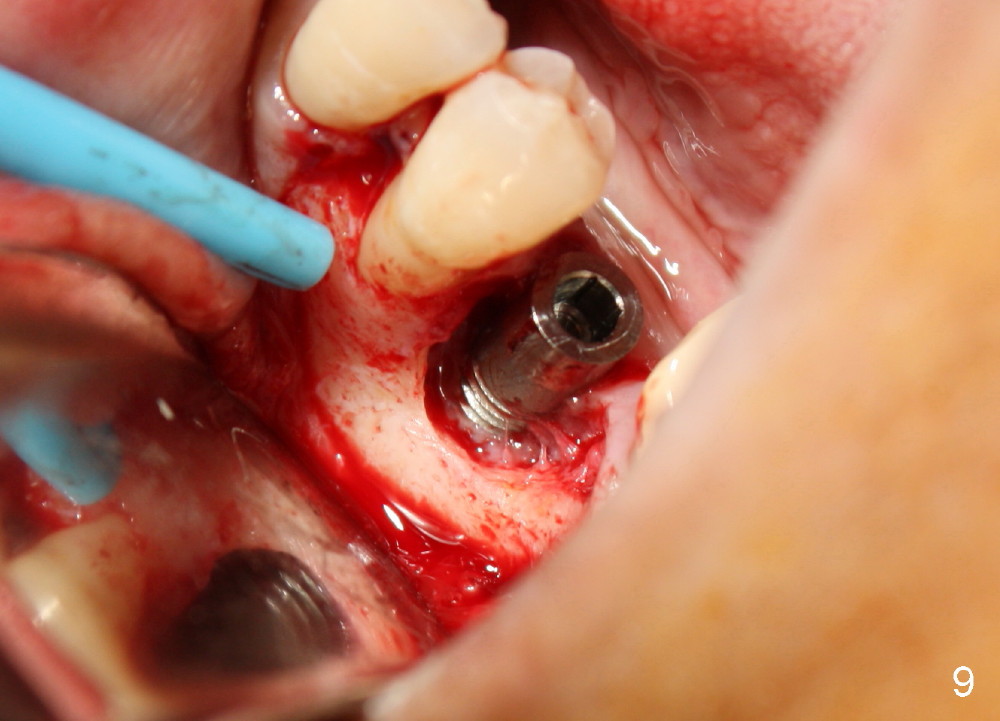

A 44-year-old lady has poor dentition. The tooth #20 has a residual root (Fig.1 R). Immediately after extraction, osteotomy is formed by drills (Fig.2: 3.5x17 mm); a 4.5x17 mm implant is placed (Fig.3 (arrowheads: boundary of the socket)). The patient returns 9 months later with increased radiolucency around the implant (Fig.4) and buccal swelling (Fig.5, asymptomatic). Raising the buccal flap confirms bone loss around the implant (Fig.6). Following debridement, allograft is placed. The source of the infection is unknown.